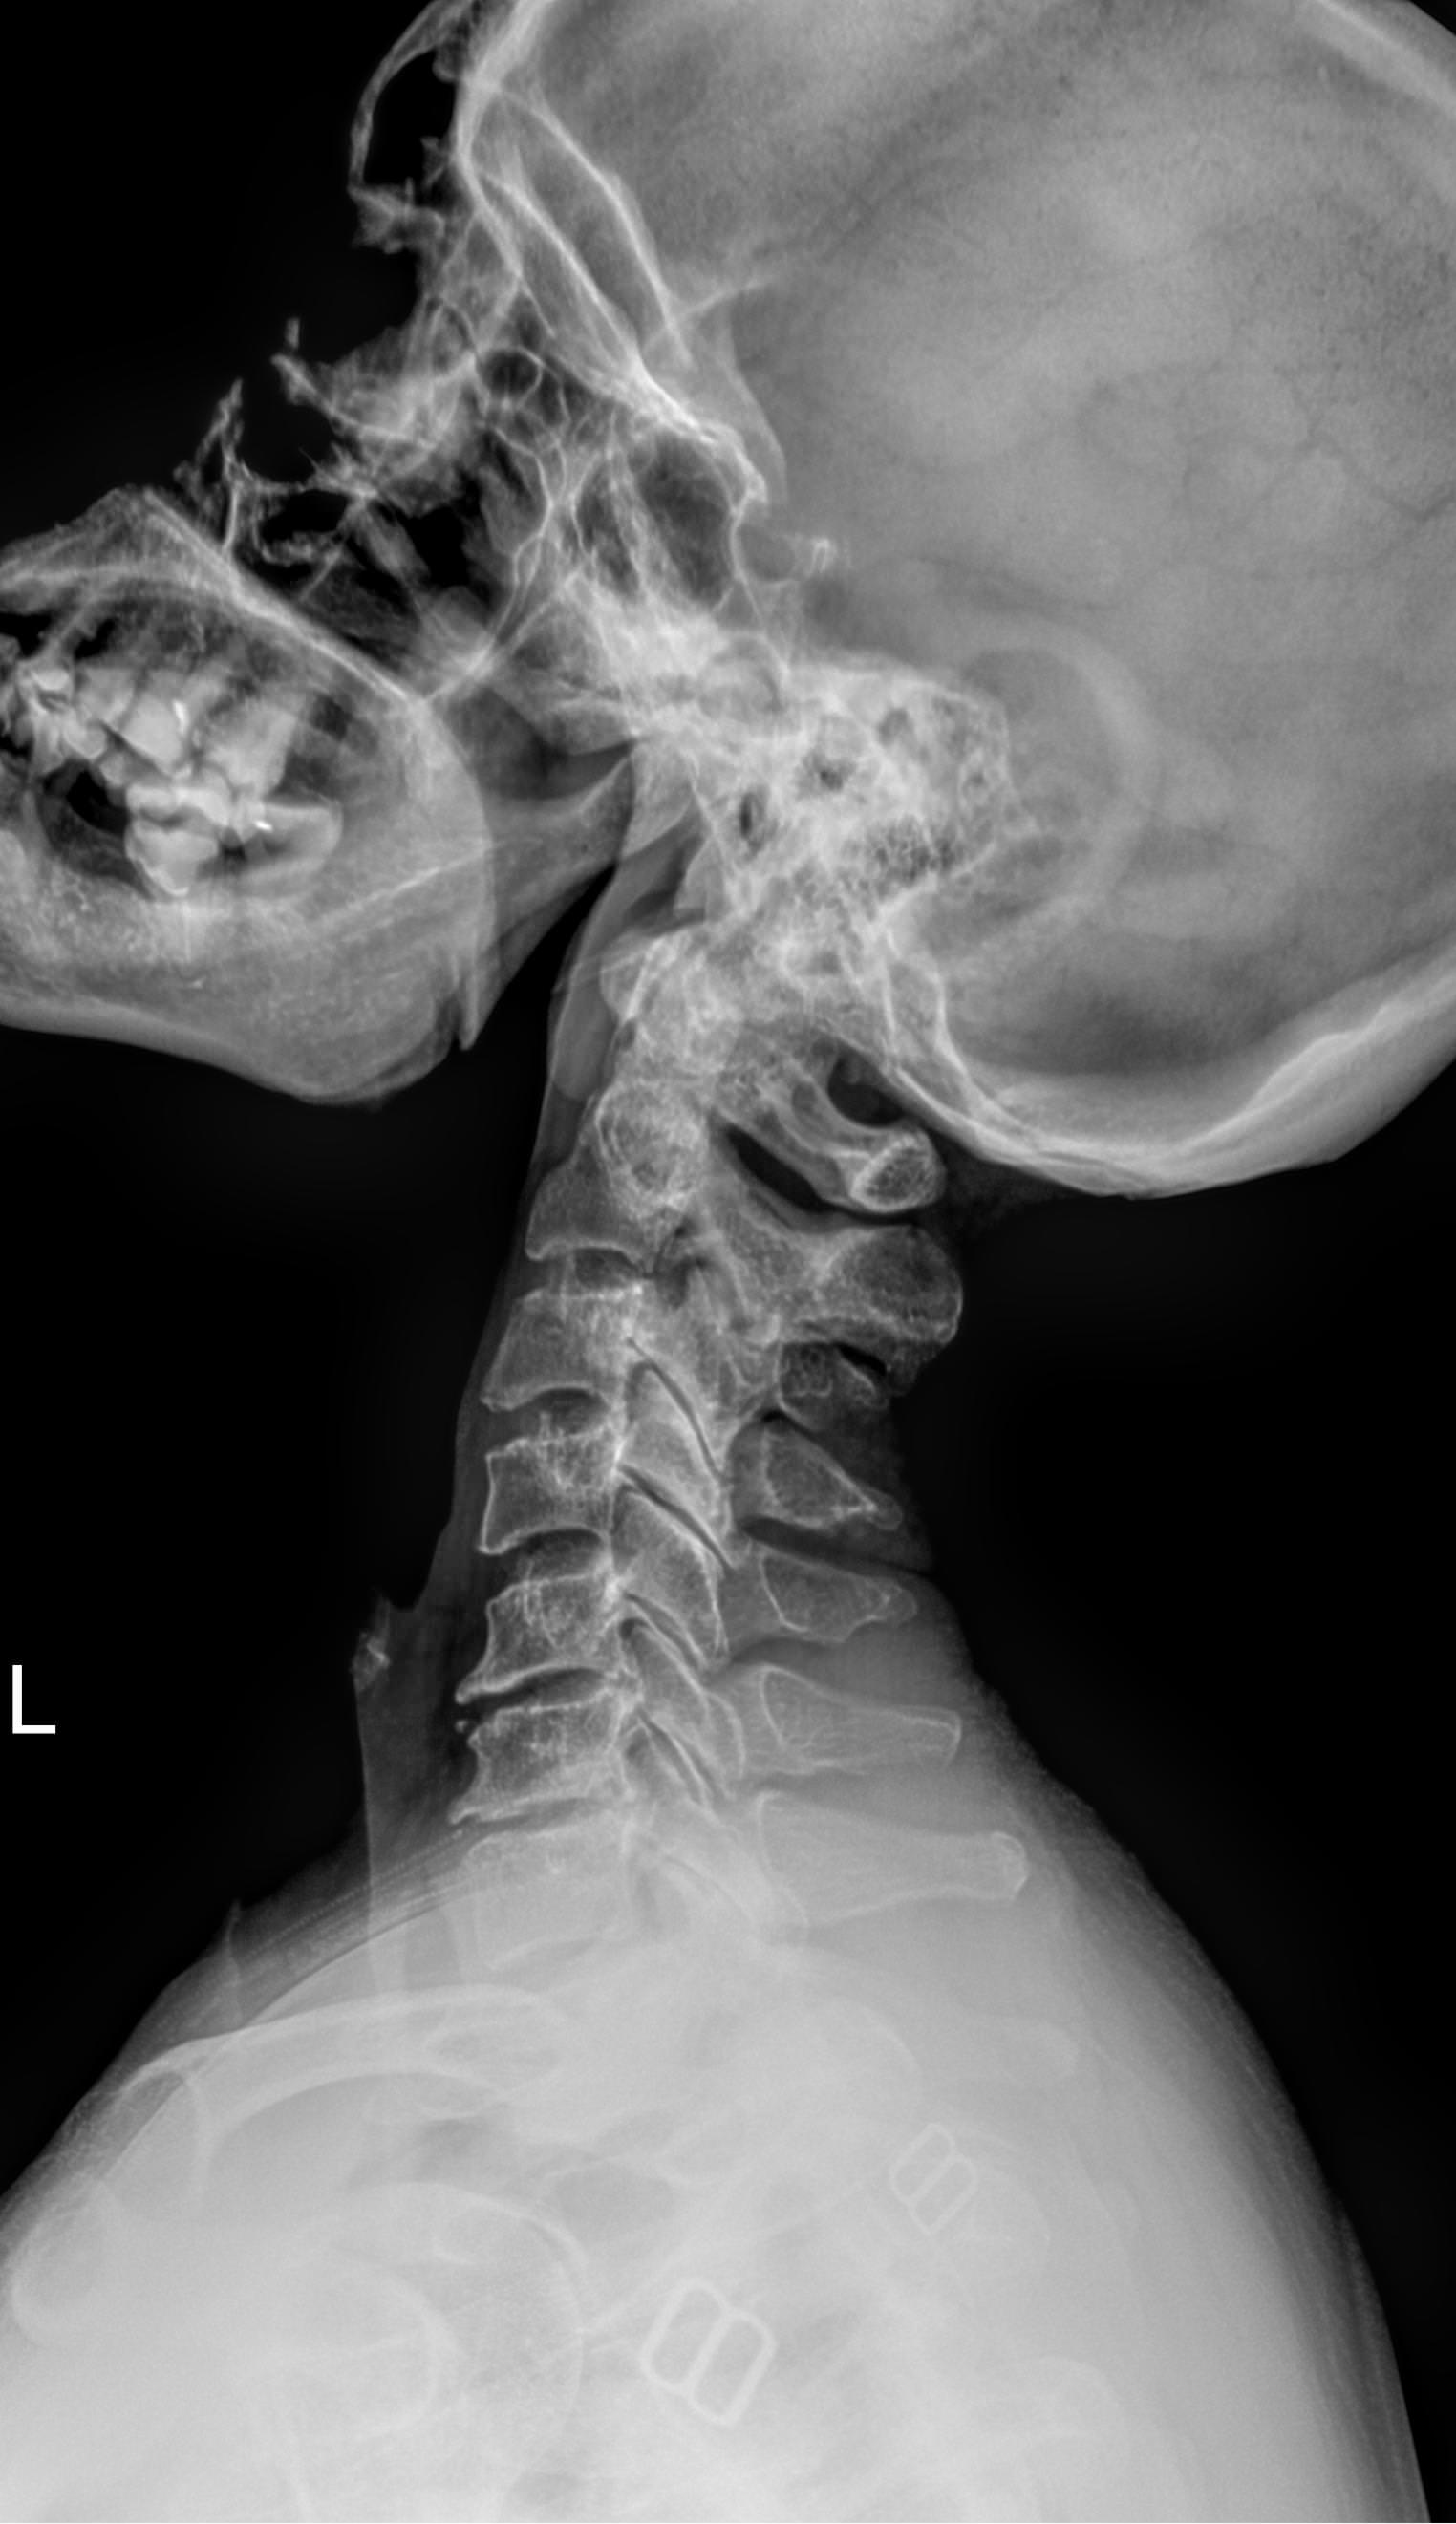

Шейный отдел позвоночника состоит из 7 небольших позвонков, в отростках которых есть отверстия для питающих голову сосудов. Этот участок позвоночного столба наиболее мобилен, однако у здорового человека движения шеи не выходят за рамки естественных. И только в случае хронических патологий наблюдается гипермобильность или, наоборот, уменьшение объема движений.

Как и другие кости, шейные позвонки отлично визуализируются с помощью рентгена. На снимках отчетливо видны признаки острых и хронических патологий, а часть врожденных аномалий обнаруживается случайно именно на рентгенограммах. В снимок попадают средние и нижние шейные, а также 2-3 верхних грудных позвонка. Для исследования двух верхних позвонков требуется специальная  проекция ― «через открытый рот».

На рентгенограмме будут видны следующие патологические изменения:

• Изменение формы тел и отростков позвонков;

• Изменение костной ткани;

• Сужение межпозвоночных пространств;

• Смещение позвонков;

• Сглаживание физиологического лордоза;

• Перелом;

• Новообразования.